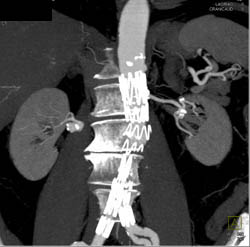

CASE NUMBER 3,554

Renal Artery Aneurysm